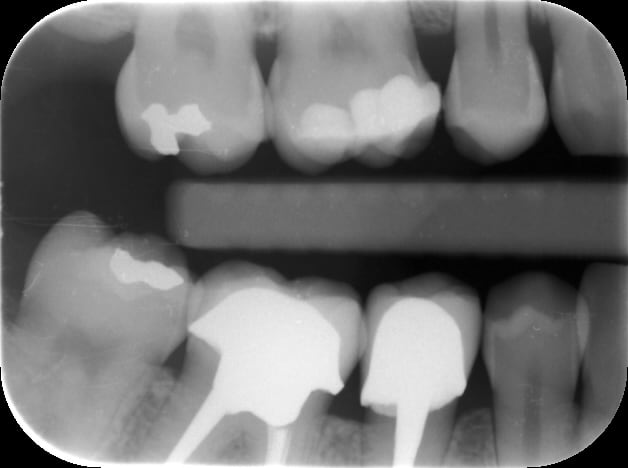

sur la première radio que tu as postée, j'appelle ça plusieurs lésions proximales, dont l'aspect me fait penser à des habitudes alimentaires néfastes à étudier avec la patiente. Si elle n'a pas une pulpite aigue, ça vaut le coup de prendre un peu de temps ... c'est juste ma petite experience perso de 10 ans bientôt. bien sûr qu'il faut sauver la 36, et la 37 et la 27 et la 35 peut être aussi tiens :)